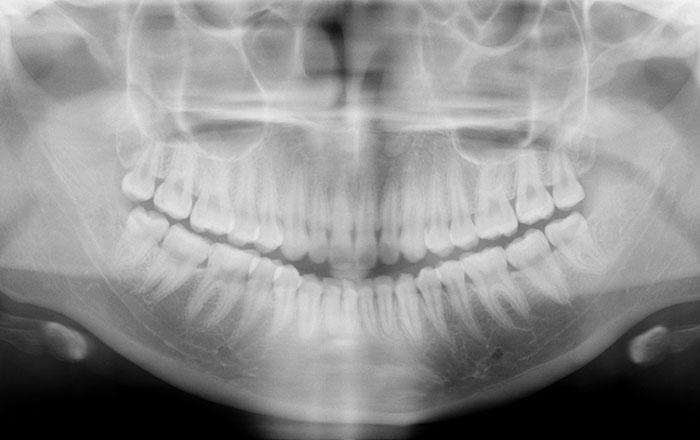

むし歯は、目視とレントゲンで進行具合を確認します。

歯周病は、歯に付着したばい菌が原因で、歯を支えている骨が破壊され、最終的に歯が揺れて抜けてしまう病気です。

骨の状態は見た目で判断できないので、プローブという器具で行う検査と、レントゲンで確認します。

また、1年に1回、お口全体のレントゲン撮影を行います。

理由は、骨の状態の確認やむし歯や歯周病がないかの確認と、歯ぐきの状態・噛み合わせが問題ないかを確認をするためです。

特に根っこの治療をした歯は、見た目では悪くなっている様子が分かりにくいので、定期的にレントゲンで経過を確認する必要があります。